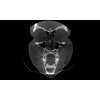

3D SNÍMKY VE VYSOKÉ KVALITĚ

Vysoce kvalitní snímky CT skeneru Planmed Verity® vizualizují i ty nejmenší kostní struktury s minimálním rušením. Izotropní rozlišení 200 μm, pokročilé algoritmy zpracování obrazu a pevné ucycení pacienta umožňují snímkování ve vysoké kvalitě. S algoritmem Planmeca CALM ™ lze zabránit zbytečným opakovaným expozicím citlivé oblasti hlavy a krku. Kromě toho je zobrazování ultra nízkou dávkou cenným doplňkem ke studiu oblasti hlavy, kde je třeba věnovat zvláštní pozornost minimalizaci radiační dávky pacienta.